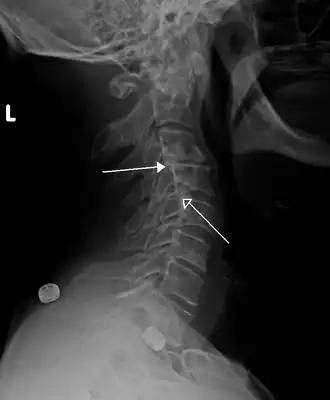

Imagen de rayos X de una anterolistesis ístmica de grado 1 en L4-5 -